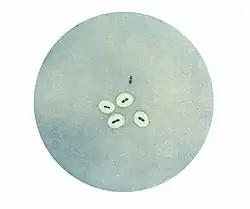

Photomicrograph of Streptococcus pneumoniae bacteria revealing capsular swelling using the Neufeld quellung test. Notice the two streptococci at the top of the photo that appear to have no capsule.

The quellung reaction, also called the Neufeld reaction, is a biochemical reaction in which antibodies bind to the bacterial capsule of Streptococcus pneumoniae, Klebsiella pneumoniae, Neisseria meningitidis, Bacillus anthracis, Haemophilus influenzae,[1] Escherichia coli, and Salmonella. The antibody reaction allows these species to be visualized under a microscope. If the reaction is positive, the capsule becomes opaque and appears to enlarge.